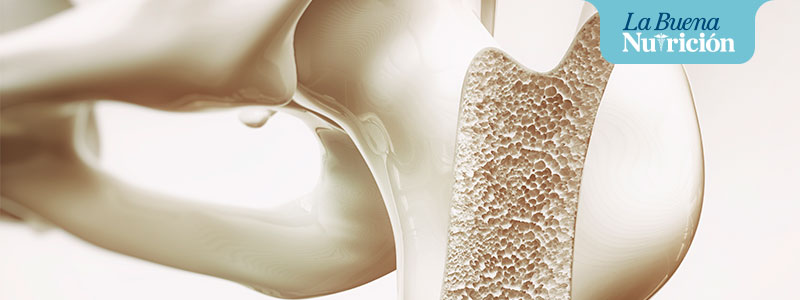

El calcio es el mineral más abundante que se encuentra en el cuerpo humano. El cuerpo almacena más del 99 por ciento del calcio en los huesos y los dientes para ayudarlos a ser fuertes y resistentes.

El hueso es un tejido que se encuentra en continuo remodelamiento y recambio; por lo cual las necesidades de nutrientes para regenerar hueso nuevo son constantes a lo largo de la vida.

La osteoporosis y la menopausia

La osteoporosis se define como una enfermedad caracterizada por una disminución de la masa ósea y la mujer puede empezar a padecer osteoporosis. Una enfermedad que puede llegar a ocasionar la pérdida crítica del hueso, o también a aumentar su fragilidad. Como consecuencia, el riesgo de sufrir fracturas se incrementa. Es en este contexto en el que la ingesta de calcio debe mejorarse, con el objetivo de que la magnitud de la reducción del remodelamiento óseo no sea intensa.

Se calcula que el 30% de todas las mujeres posmenopáusicas padecen osteoporosis; y más del 40% de éstas pueden llegar a sufrir una o más fracturas por fragilidad a lo largo de su vida.

El calcio es necesario para el desarrollo y el mantenimiento del esqueleto y de las funciones neuromuscular y cardíaca; la evidencia científica señala una fuerte asociación entre baja ingesta y disminución de la densidad mineral ósea (DMO), por lo tanto, la ingesta adecuada de este mineral puede tener impacto en la reducción de las fracturas originadas por osteoporosis. Se estima que un incremento de masa ósea del 10% podría reducir el riesgo de las fracturas en un 50%.